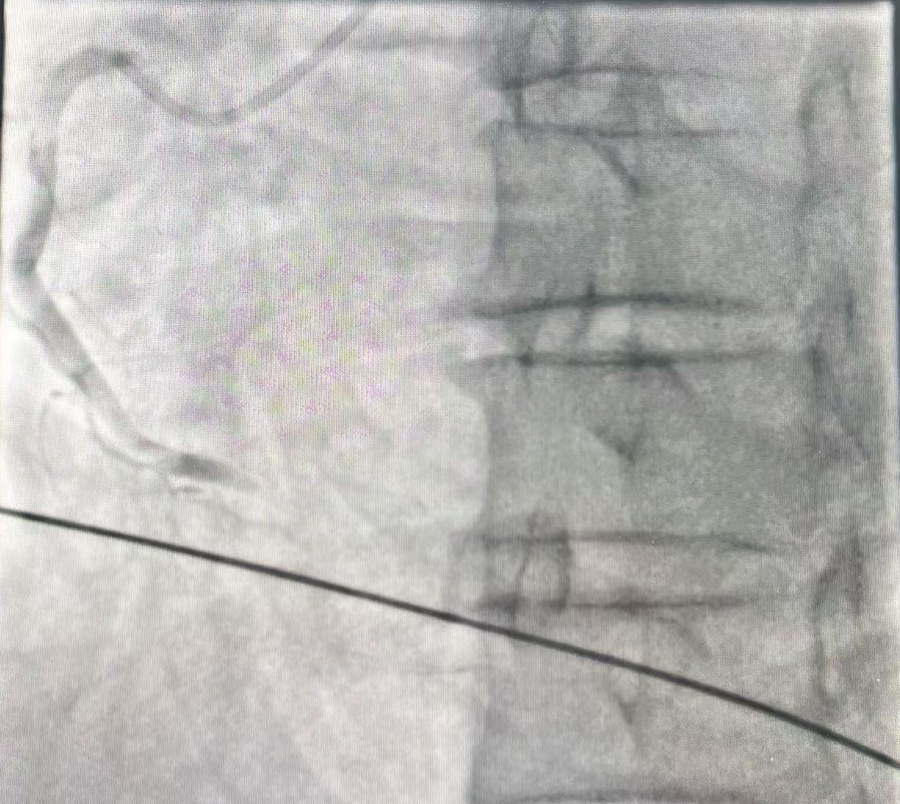

医生检查发现:郭先生是急性心肌梗死,心脏右冠状动脉的远端已经完全闭塞,没有任何血流通过;之后经手术植入心梗支架后,郭先生终于转危为安。

右冠状动脉的远端完全闭塞,没有任何血流通过